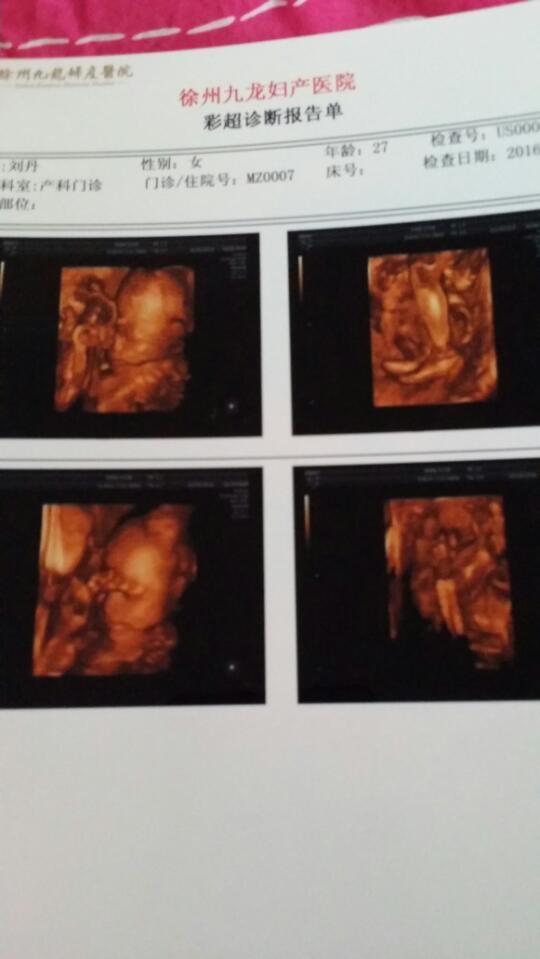

四维彩超上面宝宝脚丫子五个脚趾头分开不明显,会不会有问题,亲们帮看看谢谢 四维彩超上面宝宝脚丫子五个脚趾头分开不明显,会不会有问题,亲们帮看看谢谢。 点击展开 美丽法贝儿 2016-04-22 21:21 为您推荐: 其他回答 不会吧,,, 宝贝Miya 2016-04-22 21:26 不知道,,, 海霞1 2016-04-22 21:26 没事,,, 132*****230_QHux 2016-04-22 21:25 还是问医生,, 可可。。 2016-04-22 21:25 没事呢*^O^*(≧3≦) 有我,你多么幸福 2016-04-22 21:25 加载更多 相关问题 宝宝百天了宝宝的脚丫子跟第二脚趾头缝儿大是怎么回事 我的脚趾头怎么了?自从生了小孩做完月子!我的脚丫子就成这样了?能好吗? 宝宝第四个脚趾头和第五个脚趾头未分开,多